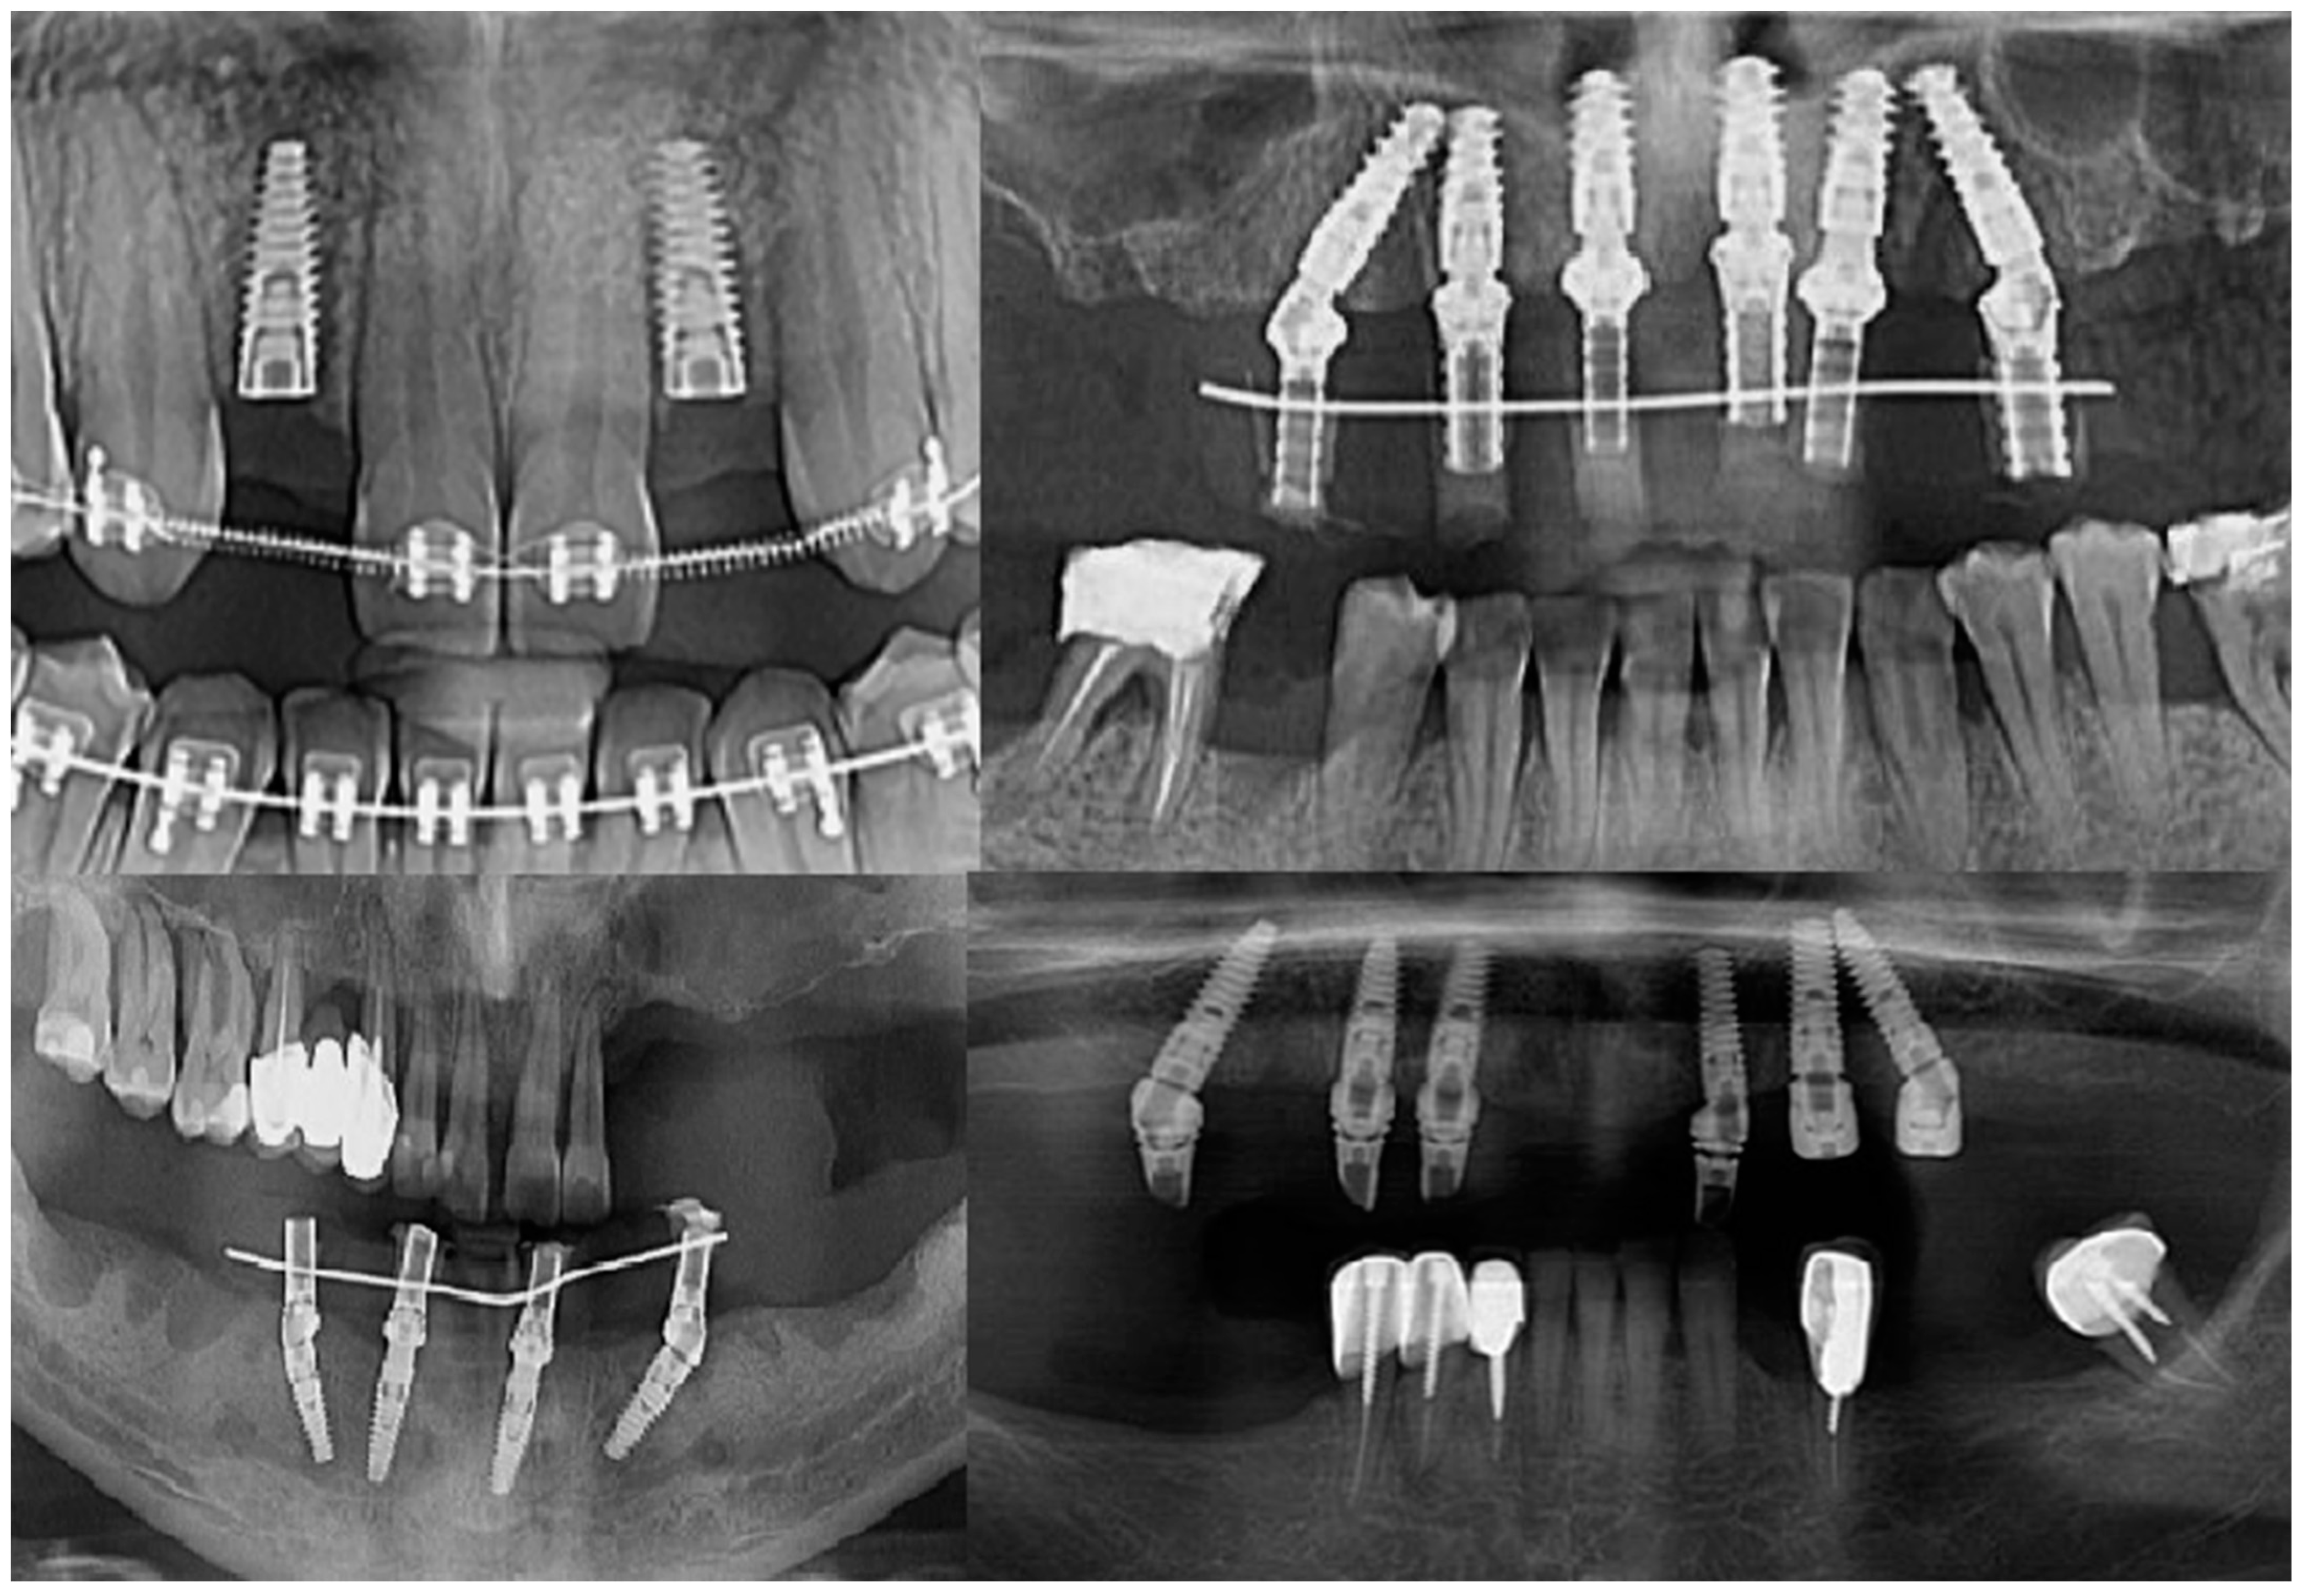

Intraoperatively, the dental implants were screwed into the alveolar bone according to the manufacturers’ indications, being applied over the dental implant with either a covering screw or healing abutment or multiunit abutment (Figure 1). The postoperative wound was sutured with Dafilon™ 4/0 suture thread (BBraun Hessen, Germany BBraun, Spangenberg, Germany) and Dafilon™ 5/0 suture thread (BBraun Hessen, Germany BBraun, Spangenberg, Germany).

Figure 1.

Radiological images presenting different clinical cases included in the study.

The follow-up of the patients was made at 1 month, 3 months, and 6 months from the moment the suture threads were removed. Retro-alveolar and OPG X-rays were performed in isometric and orthoradial incidences using the Belot method [16] (Figure 3). In cases where any kind of suppurated complications occurred less than a month after the insertion, the dental implant was removed.

Figure 3.

Radiological images of clinical cases during the follow-up period.